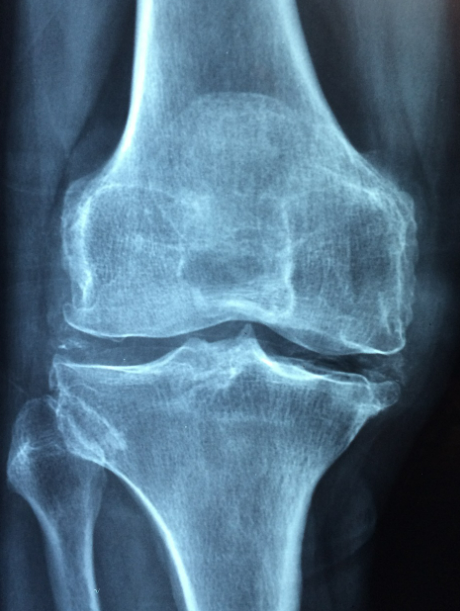

무릎에 물이 차는 증상을 진단하기 위해서는 의료 전문가의 진료가 필요합니다. 의사는 환자의 증상과 질병 기록을 조사하고, 신체 검사와 필요에 따라 영상 검사를 시행할 수 있습니다.

X-레이, 초음파, MRI 등의 영상 검사를 통해 무릎 내부의 상태를 확인할 수 있습니다. 진단을 통해 증상의 원인을 파악하고, 적절한 치료 계획을 수립할 수 있습니다.